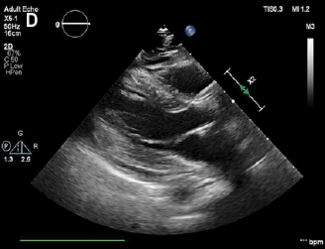

Although some of the causes of myocardial infarction with no coronary artery obstruction (MINOCA) are often unknown, spontaneous coronary artery dissection (SCAD) in MINOCA should always be considered early on as one of the major etiologies...